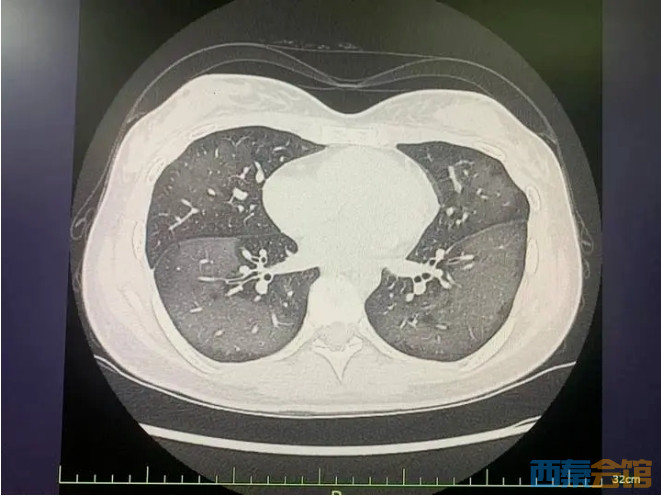

该院急诊科的主治医师童娅玲接诊了丽丽,经CT检查发现,丽丽的双肺呈现大范围白色样病变,报告提示“白肺”。

患者肺部CT

丽丽被诊断为“急性过敏性肺炎”,急诊专家对丽丽给予吸氧、激素抗炎抗过敏等对症支持处理后,急性症状得到缓解,她被收入呼吸内科病房进一步住院治疗。

急诊科主任陆远强主任医师解释,此类“白肺”与使用防晒喷雾时吸入的有害物质有关,喷雾中的某些化学成分会刺激诱发一系列过敏反应,从而导致广泛的气管、支气管乃至肺水肿,让肺部无法正常工作。